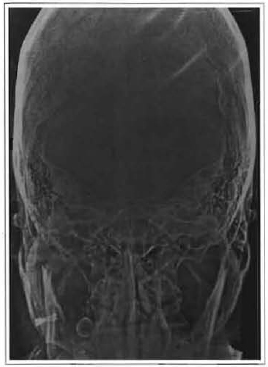

The patient began a physiotherapy program after removal of the maxillomandibular immobilization. Four months after surgery the patient presented a mandibular deviation towards the affected side, along with inadequate occlusion due to shortening of the left mandibular branch (Fig. 3). The patient was referred to an orthodontist to correct occlusion impairment. After 6 months of orthodontic treatment, proper occlusion was not obtained. (Fig.4). The x-ray at the time showed complete resorption of the condyle (Fig.5).

Fig. 3 -Front view of a patient with left mandibular deviation due to shortening of the ipsilateral mandibular branch.